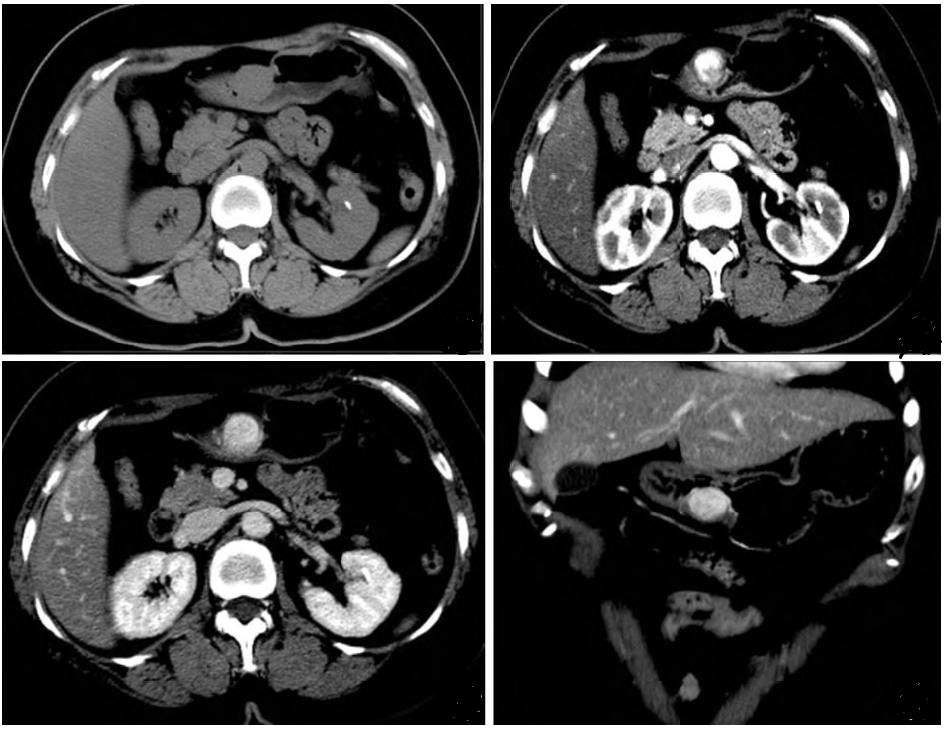

图2:动脉期图1:平扫全身pet/ct示:胃窦小弯侧内凸结节,代谢稍增高

性结节样肿块,边缘光滑跨壁生长低密度肿块,密度均匀;多位于胃窦肌层

上腹部ct平扫,发现胃窦小弯侧壁增厚. 建议增强ct扫描